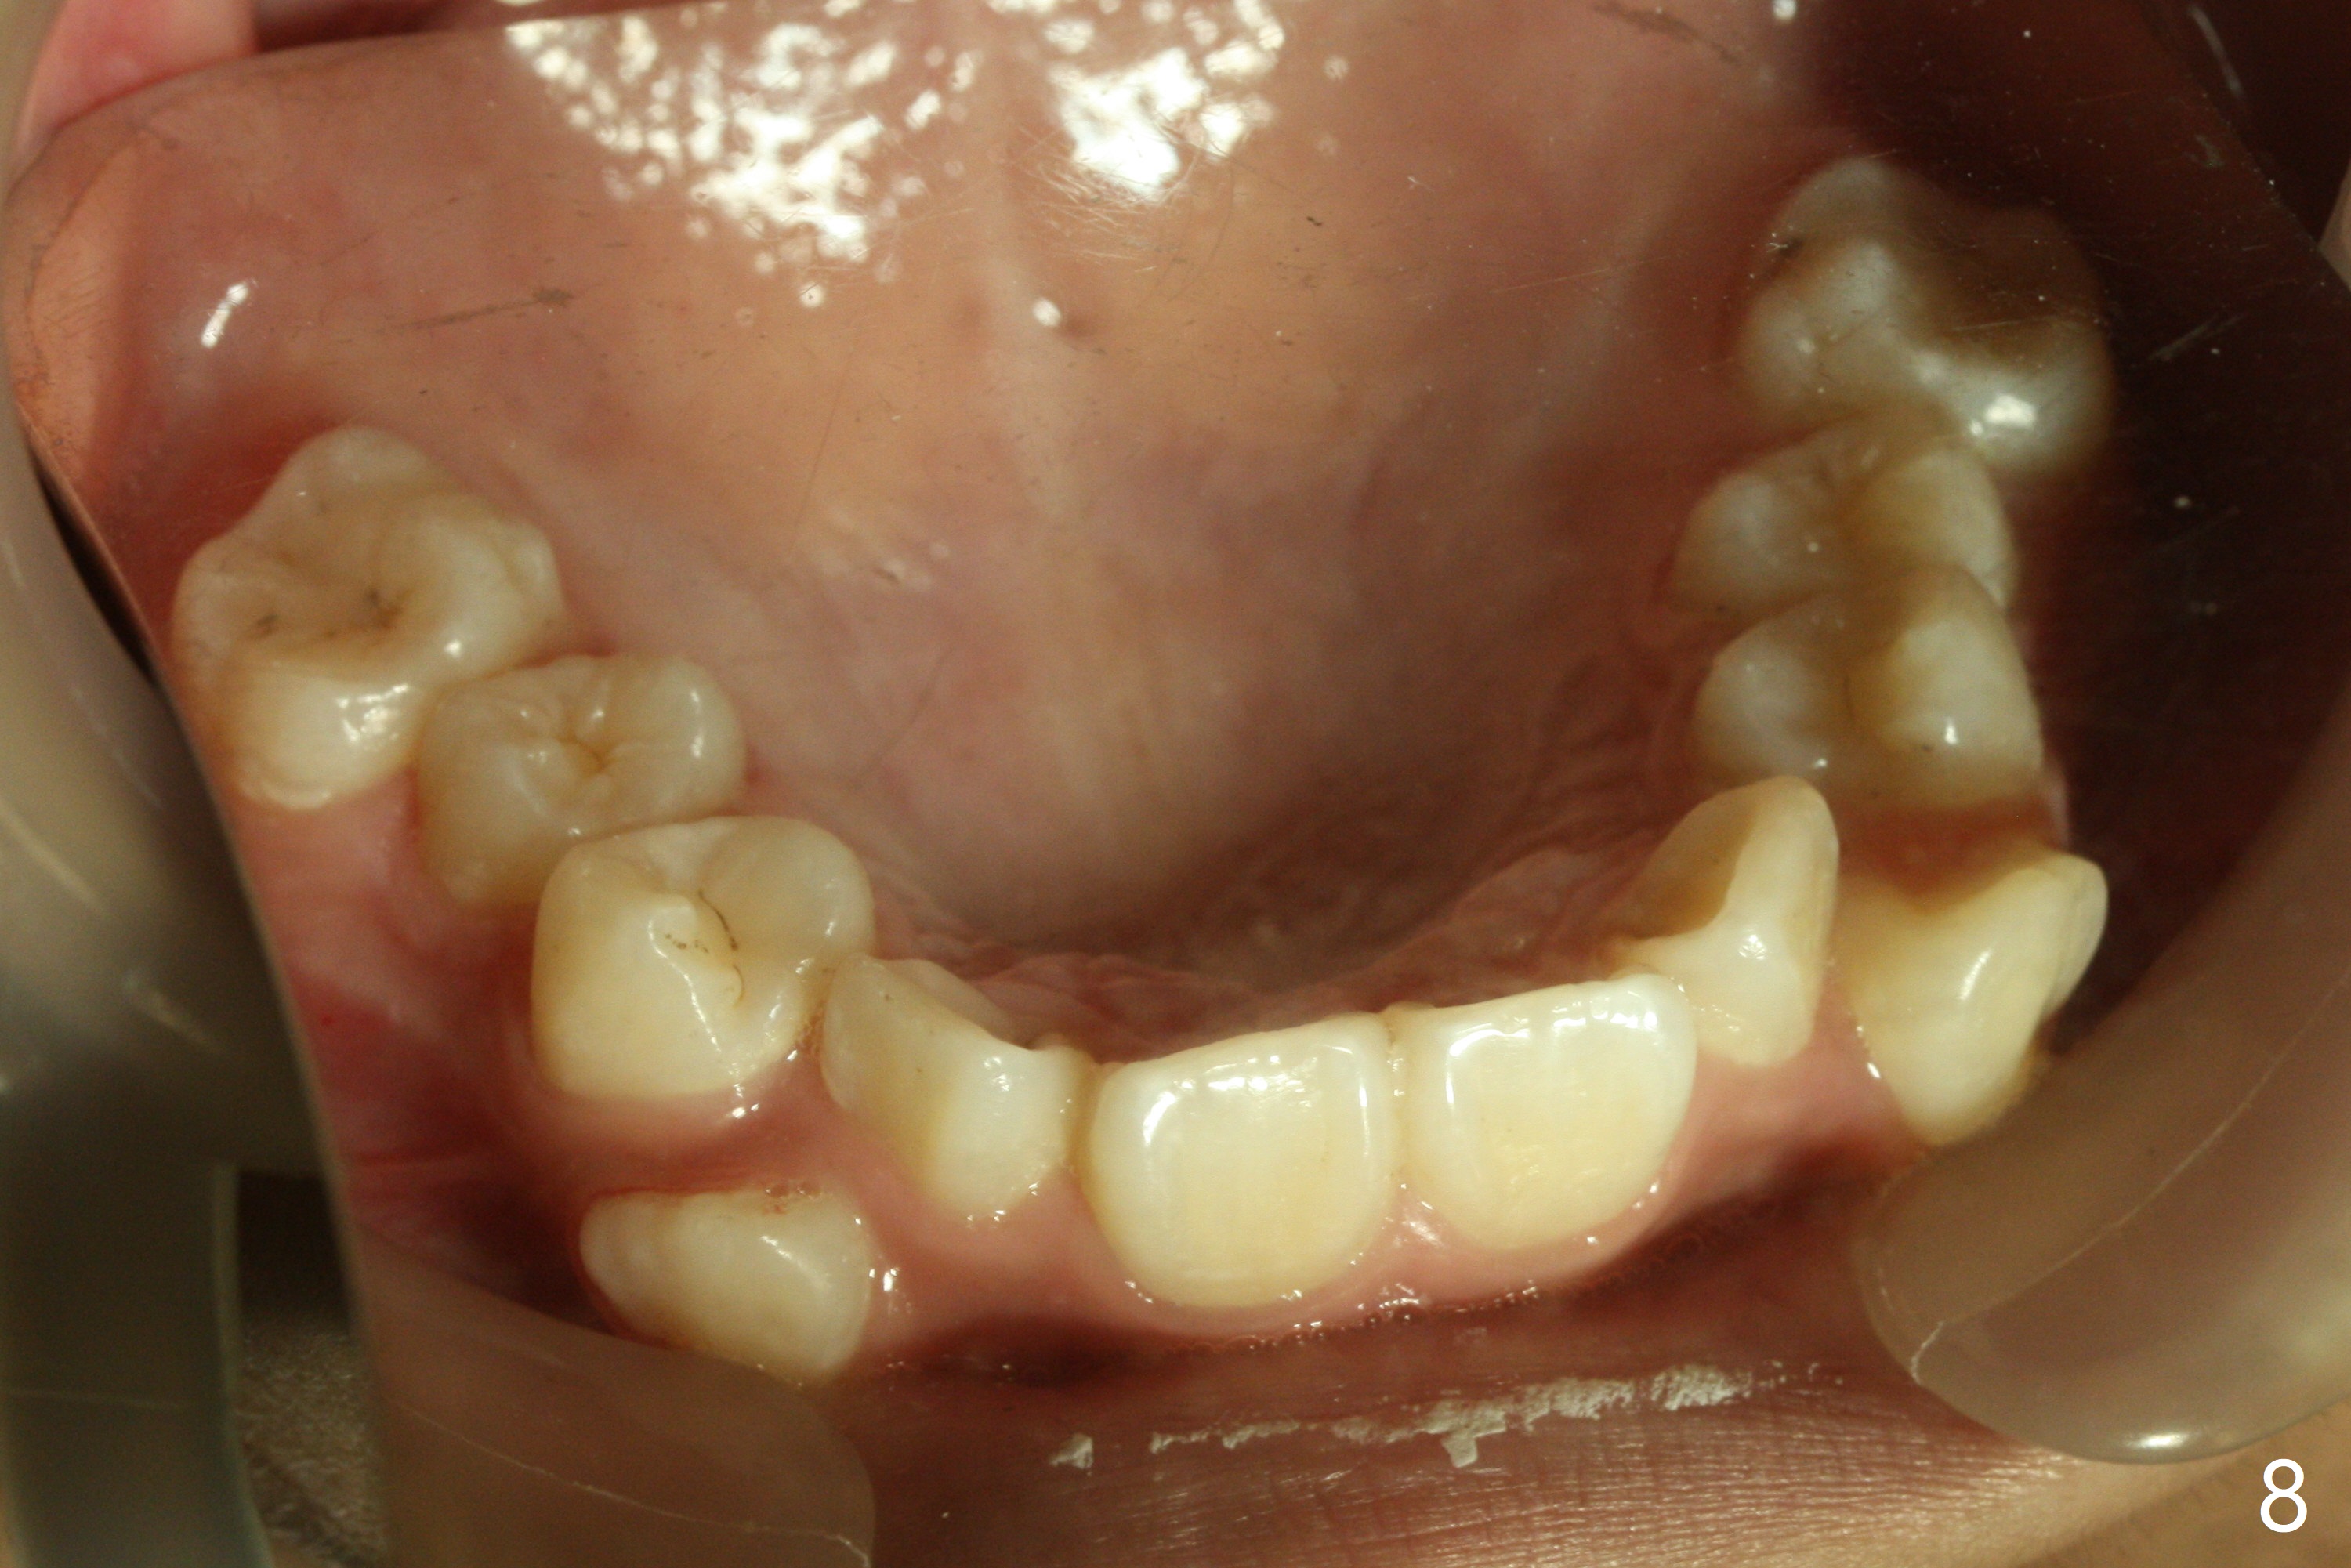

Severe crowding with normal facial profile appears to dictate extraction of 4 bicuspids and of the lower 2nd primary molars (Fig.1-11).  Since there is no time for banding before school, delay in orthodontic treatment post extraction will lose space?

Dear Dr. Shaughnessy: can you open the following link?  I would like to try to extract 4 bicuspids and 2 lower primary 2nd molars and let the canines shift by themselves.  But I wonder whether the 2nd permanent bicuspids, especially the upper ones, may shift mesially instead.  How would you like to handle the situation?